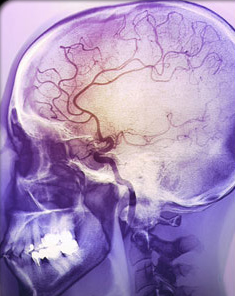

Efforts to correct blood pressure during ischemic stroke (the most common kind) worsen brain damage from lack of blood flow, also called ischemia. Rose and Mayer propose that blood pressure normalization with medications exacerbate ischemia in part because of impaired autoregulation of the arteries in the brain areas around the stroke. Autoregulation is the adjustment of vasoconstriction or vasodilation of brain arteries that usually optimizes flow and oxygen delivery to the brain.

What if, instead, the changes in blood pressure that occur during many strokes, in fact, help the injured brain tissues surrounding an area of stroke (the penumbra) receive sufficient blood and oxygen?

It is possible that higher than normal blood pressure during a stroke might be the brain’s way of “making the best of a bad job.” If so, that adjustment in blood pressure might be an adaptation that preserves blood flow to damaged brain after infarction (stroke because of a blood clot) or injury. This “new normal” blood pressure finding during stroke could be an adaptation that evolved because of natural selection.